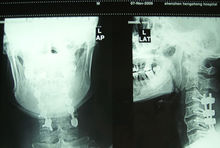

手術時機

頸髓損傷的手術固定頸椎脊髓傷的治療目的包括:頸椎穩定性的重建和脊髓功能的恢復兩個部分。在很長一段時間內,以牽引外固定為

主的保守治療被廣泛套用於臨床,並被認為有較滿意的結果。然而,保守治療不可能使脊髓損傷有實質性改善,反而可能因重複微創傷阻礙神經功能恢復。此外保守治療固定不夠切實,即使是被認為最佳的頸部外固定裝置Halo背心也無法避免後期發生的頸椎畸形及頸後韌帶鬆弛。更為重要的是傷後長期臥床使併發症發生率增大,從而增加了死亡率。